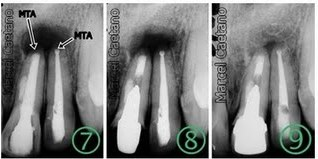

Paciente apresentou-se com lesão periapical veja RX inicial, foi indicada a cirurgia e no ato foi retirado material para exame histopatologico, para se descobrir a natureza da lesão.

Notar que a raiz do dente vizinho esta inclinada pela presença da lesão, suspeita de Cisto.O Cisto aumenta de tamanho sempre causando grande perda óssea, causando se não tratado deformidade óssea e dental podendo ser fatal.

Após com redução da perda óssea